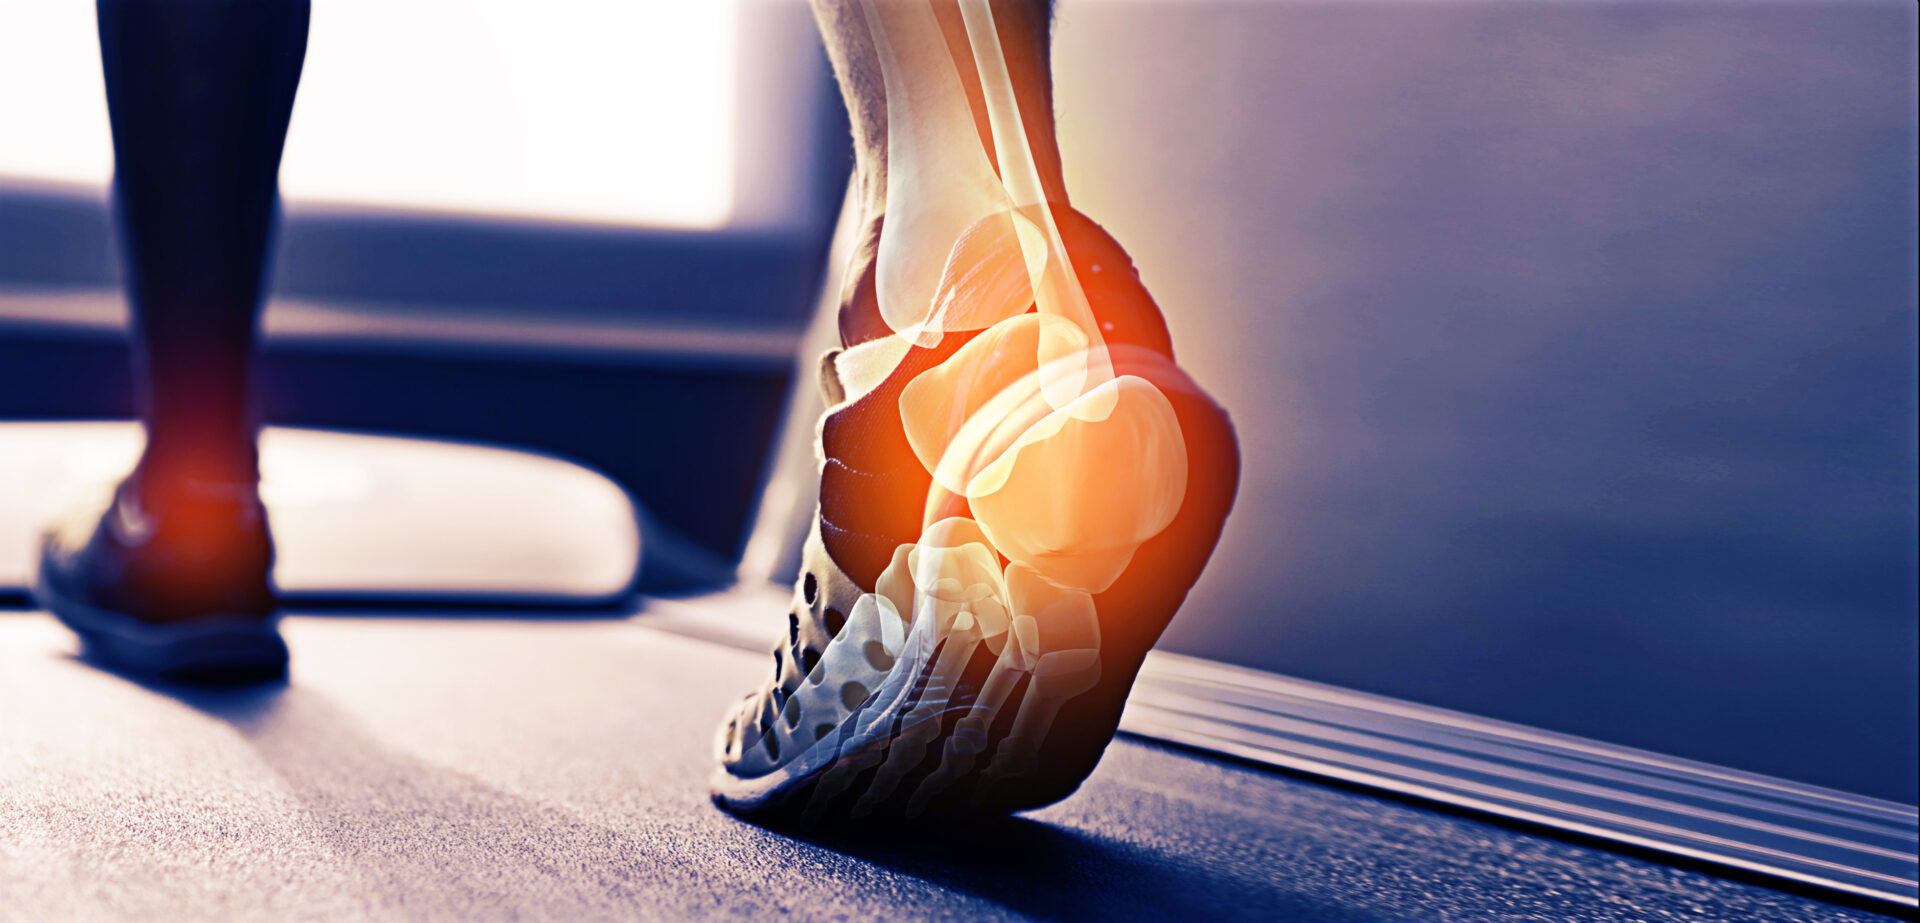

Distorsione alla Caviglia.

Distorsione alla caviglia, perché non va sottovalutata.

Molti pensano che una distorsione alla caviglia si possa risolvere solo con il tempo. Sbagliato!

Il trattamento Osteopatico di una caviglia distorta è molto indicato: aiuta a riposizionare le ossa del piede e ad allentare le tensioni legamentose. In tal modo si recupera la mobilità in maniera completa e naturale.

Trascurare una distorsione può portare nel tempo a una sintomatologia cronica caratterizzata da sinoviti, tendinopatie, rigidità, aumento di volume, dolore e insufficienza muscolare, associati o meno a instabilità del collo del piede con difficoltà a deambulare su terreni irregolari o episodi distorsivi recidivanti e nel tempo, tutte queste problematiche, possono portare a una vera e propria problematica posturale.